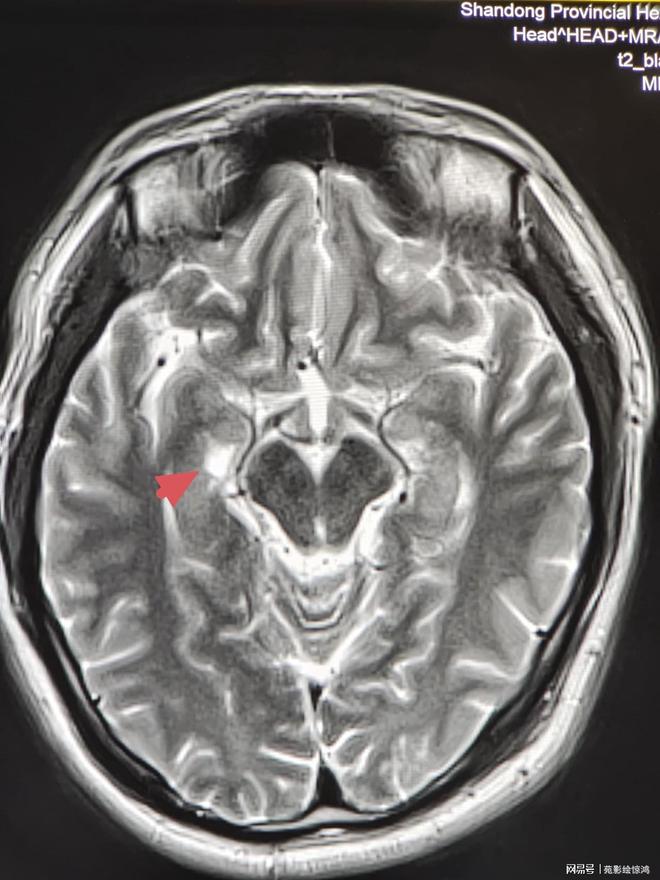

左侧中颅窝蛛网膜囊肿的严重程度因人而异,需综合评估囊肿大小症状及并发症等因素若囊肿较小且无症状,通常不严重此类囊肿若未压迫周围脑组织,不影响颅内结构或功能,一般无需特殊治疗,仅需定期复查如每612个月进行头颅CT或MRI检查,观察囊肿是否增大或出现新症状若囊肿较大或引发症状。